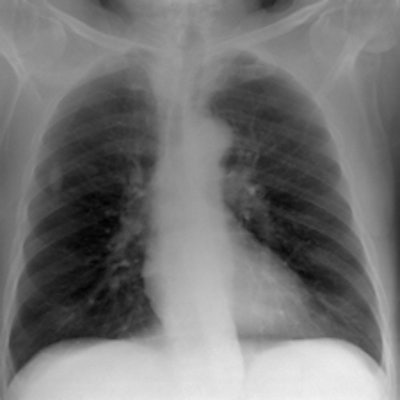

Simulated chest images of an average-sized patient reconstructed at 50 kVp (a) and 150 kVp (b). Image (a) is of higher contrast, which is expected. All images courtesy of Craig Moore.For average-sized patients, image quality improved when tube potential was reduced compared with the reference (102 kVp) and no scatter rejection was indicated. For obese patients, it has been shown that an antiscatter grid is indicated and should be used in conjunction with as low a tube potential as possible (while allowing exposure times, 20 msec), the researchers wrote. It is also possible to reduce receptor air kerma by 50% without adversely influencing image quality. They also found rib contrast did not interfere at any tube potential.

Simulated chest images of an average-sized patient reconstructed with an antiscatter grid (a) and without a grid (b). Image (a) provides greater detail, especially in the denser regions of the chest, which is expected."Although there is a trend toward increased image quality at low tube potentials, it was only possible to statistically distinguish between 50 and 90 kVp, 80 and 90 kVp, and 80 and 109 kVp," Moore and colleagues wrote. "All other combinations demonstrated p-values > 0.102. Nevertheless, these results show that for matched effective dose, image quality improves with lower tube potentials, which is similar to results reported in the literature."